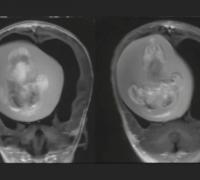

Menina passa por cirurgia para retirar feto de irmão gêmeo do crânio

Imagem: reprodução. O feto de 10 centímetros foi descoberto após a criança passar por exames de imagem que investigavam problemas de desenvolvimento motor Uma menina chinesa de 1 ano passou por uma cirurgia delicada para retirar o feto de seu irmão...